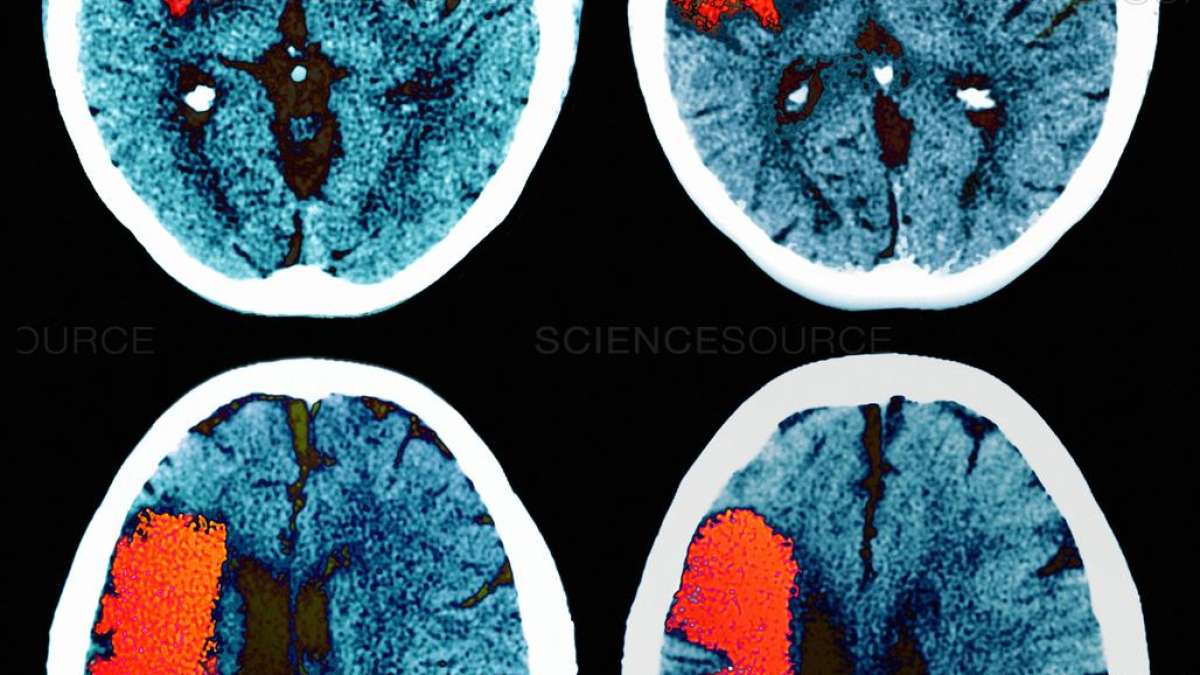

Đột quỵ và mất trí nhớ: chiến đấu với sự mất mát chức năng trong các mạch máu não nhỏ

Một nghiên cứu mới nhận diện các nhân tố phân tử thúc đẩy bệnh ở mạch máu nhỏ - và một loại thuốc có thể giúp phục hồi các chức năng mạch máu bị suy giảm.